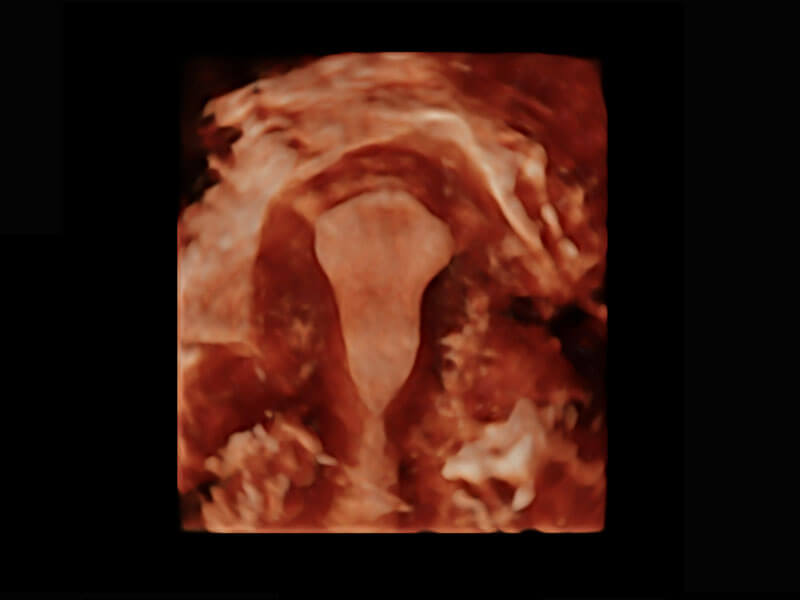

• 腔内三维-宫内节育器

• 腔内三维-光影成像